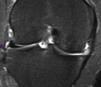

En la RM, el implante meniscal era del mismo tamaño que el menisco normal (tipo 3) en 5 de los pacientes un año después de la cirugía (fig. 2), pero al final del seguimiento el tamaño había disminuido en todos los pacientes. En ninguno de los casos la morfología se clasificó como de tipo 1, ya sea a los seis meses, doce meses o en el seguimiento final. La intensidad de la señal de RM disminuyó progresivamente pero no llegó a ser en ninguno de los casos igual a la de un menisco normal.

En uno de los pacientes, el de mayor edad y con peor evolución, la RM mostró dos años después de la cirugía extrusión del implante con una morfología de tipo 2 y un tipo de señal 1 (fig. 3). Se realizó una artroscopia debido a la persistencia del dolor observándose una progresión de los cambios degenerativos del cartílago del cóndilo medial (ICRS 3). El implante se hallaba completamente integrado con el cuerno anterior del menisco, con una morfología similar a la de un menisco normal en este área (fig. 4A), pero en su zona posterior mostraba fibrilación y rotura, con un color amarillento (fig. 4B). La biopsia realizada en la zona media del implante mostró la presencia de fibrocartílago con características similares a la de los menisco normales en la hematoxilina y eosina (fig. 5). El implante se dejó in situ y se retiraron las suturas que eran visibles.